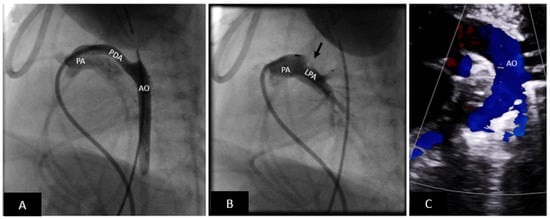

- Device related left pulmonary artery stenosis is an important consideration especially in small infants. Intraductal placement of the device and using a device without a disc on the pulmonary artery side are useful strategies.

- iv.

- Device-related aortic coarctation can occur. The risk is highest in small infants and neonates. Mild isthmic hypoplasia, protrusion of the device into the aorta, and short length of the PDA are some of the risk factors.

- Arterial injury: Until recently, arterial access was needed to perform assessment for residual shunting and arch obstruction prior to device release. The risk of arterial injury is highest in small infants. In premature infants, arterial access is not obtained; assessment for left pulmonary artery stenosis, aortic obstruction, and residual shunting is performed using transthoracic echocardiography. Many operators are now extending this experience to larger infants, further increasing the safety of the procedure.